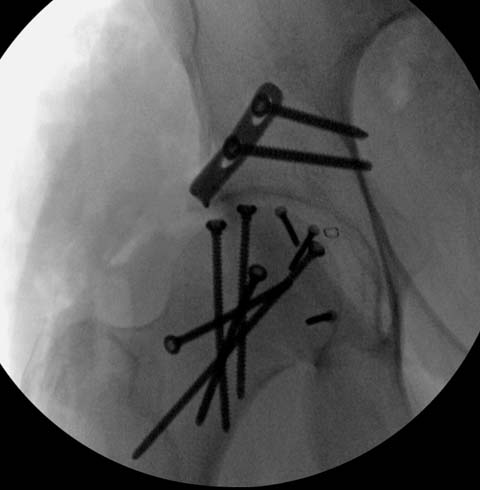

Далее перевод к нам в Травмоцентр и 03.03.2015. через 8 дней операция, выполнен остеосинтез головки 3-мя самокомпрессирующими винтами Autofix под разными углами с погружением в субхондральный слой. Доступ Kocher-Langenbeck с флип-остеотомией большого вертела и задним хирургическим вывихом головки бедра. В полости сустава два свободно-лежачих фрагмента хряща головки, которые были удалены. На снимках виден дефект хряща головки после репозиции. Небольшой фрагмент заднего края фиксирован двумя спонгиозными винтами. Далее шов раны с дренированием. На 2 сутки пациент поворачивался на здоровый бок с валиком между ног, на 4 сутки сидел в кровати и на 6 сутки ходил с помощью костылей.

Здесь выбрана правильная тактика и операция сделано на хорошо. Надеюсь, промах с фиксацией не создаст проблему. Можно было добавить в задную стенку spring plate и винты до медиального кортекса в фиксации вертела.

Здесь клинические примеры: Первый случай передний доступ, второй с ICP monitor Flipp Trochanteris

и с переломом заднего края.